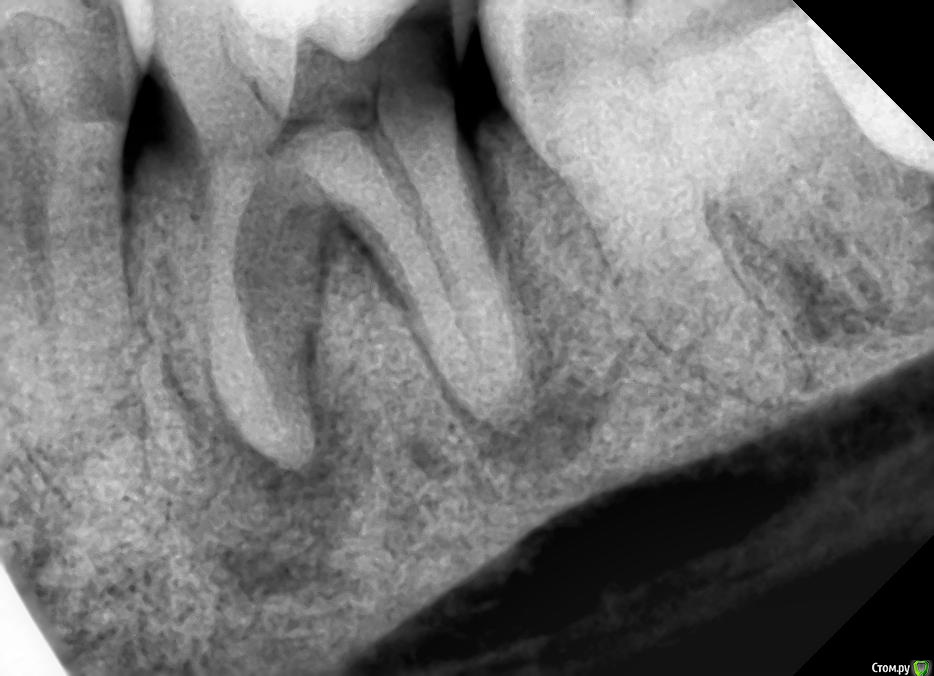

Ирвин Опубликовано 26 мая, 2016 Поделиться Опубликовано 26 мая, 2016 Лечить нельзя удалять. Зуб 3.6.Вся поверхность зуба очень чувствительна к прикосновениям и всяким соленьям и маринадам. Не трогаешь, ничего не беспокоит. Зуб немного шатается, если прилагать усилия.Прошлой осенью было, видимо, обострение, не только было больно прикасаться, но и ныл ещё порядка месяца.Был на приёме у стоматолога, он сказал, что гиперчувствительность эмали, пройдёт. Был только визуальный осмотр, без снимков. Обострение, действительно, прошло, но повышенная чувствительность (если сравнивать с другими зубами) осталась.Зуб с пломбой. Делали очень давно, более 20-ти лет назад. На днях сделал снимок (прилагается) на нём вот такая картина.Что делать? Ссылка на комментарий

shishok Опубликовано 26 мая, 2016 Поделиться Опубликовано 26 мая, 2016 Там скрытый кариес на задней поверхности(достаточно глубокий).Я бы попыталась полечить.ИМХО. Ссылка на комментарий

vse32 Опубликовано 26 мая, 2016 Поделиться Опубликовано 26 мая, 2016 Там скрытый кариес на задней поверхности(достаточно глубокий).Я бы попыталась полечить.ИМХО.Там отлом небной стенки. Я этот зуб видела. Ссылка на комментарий

Jurai Опубликовано 26 мая, 2016 Поделиться Опубликовано 26 мая, 2016 Отличный качественный периодонтит. Стоит попытаться лечить. Ссылка на комментарий

Ирвин Опубликовано 29 мая, 2016 Автор Поделиться Опубликовано 29 мая, 2016 (изменено) Фото покажите Фото зуба, о котором шла речь. Зуб, как вы знаете, удалён. Поэтому фото не во рту. Разрезан был при удалении, не мной. Забрал его без каких-либо задних мыслей. Так всегда делаю, есть ещё два зуба мудрости.В посте об удалении не написал исключительно потому, что не хотел отвлекать внимания от снимка, так как окончательное решение об удалении принималось врачом на основании его. До этого, по результатам визуального осмотра врачом, в ходе которого и произошёл отлом нёбной стенки (на зубе была вертикальная трещина посередине внутренней стороны, она, собственно, и заставила меня этим зубом заняться, всё равно, рано или поздно трещина бы разошлась, плюс ещё повышенная чувствительность поверхности), было принято решение о лечении, так как мне было сказано, что можно поставить пломбу, поскольку граница отлома не уходит под десну. Затем каким-то прибором проверялись нервы на реакцию на пропускание, судя по всему, электрических импульсов. Зуб, а с ним и я, на это никак не реагировали, в связи с чем было сказано, что нервы мёртвые и что это уже плохо, после чего был сделан снимок и принято решение об удалении, так как на снимке, со слов врача, имеется карман с дистальной стороны на всю длину корня и кисты, может быть ещё что-то, я не помню, не специалист. Никакого предложения о том, чтобы сделать диагностическое препарирование зуба не было. Это то, что я могу сказать с точки зрения пациента в части, касающейся принятия решения об удалении зуба. Врач, видимо, изложил свой взгляд и аргументы в своём посте в «Терапии для врачей», я его видеть не могу, но, поскольку, как здесь, в моём посте, так и в теме для врачей, комментарии его коллег явно не его в пользу, как и его (врача) ответы на эти комментарии, особенно ответы, хотелось бы разобраться в ситуации настолько объективно, насколько это возможно. Так как, исходя из её ответов на комментарии профессионалов, у меня теперь складывается впечатление о том, что основными факторами, способствующими принятию решения об удалении зуба было не столько его состояние, а неуверенность в результатах лечения, то, что я не родственник, чтобы биться до последнего и недостаток времени в связи с ожиданием следующего пациента.Если пугала ответственность, логичнее было бы отказаться от лечения вообще и отправить к более опытному врачу, чем упрощать процесс до удаления. Последние две причины вообще за гранью моего понимания. Хорошо, что врач не хирург и речь о зубе, а не о руке или ноге. Ещё раз всем спасибо за комментарии! Изменено 29 мая, 2016 пользователем Ирвин 1 Ссылка на комментарий